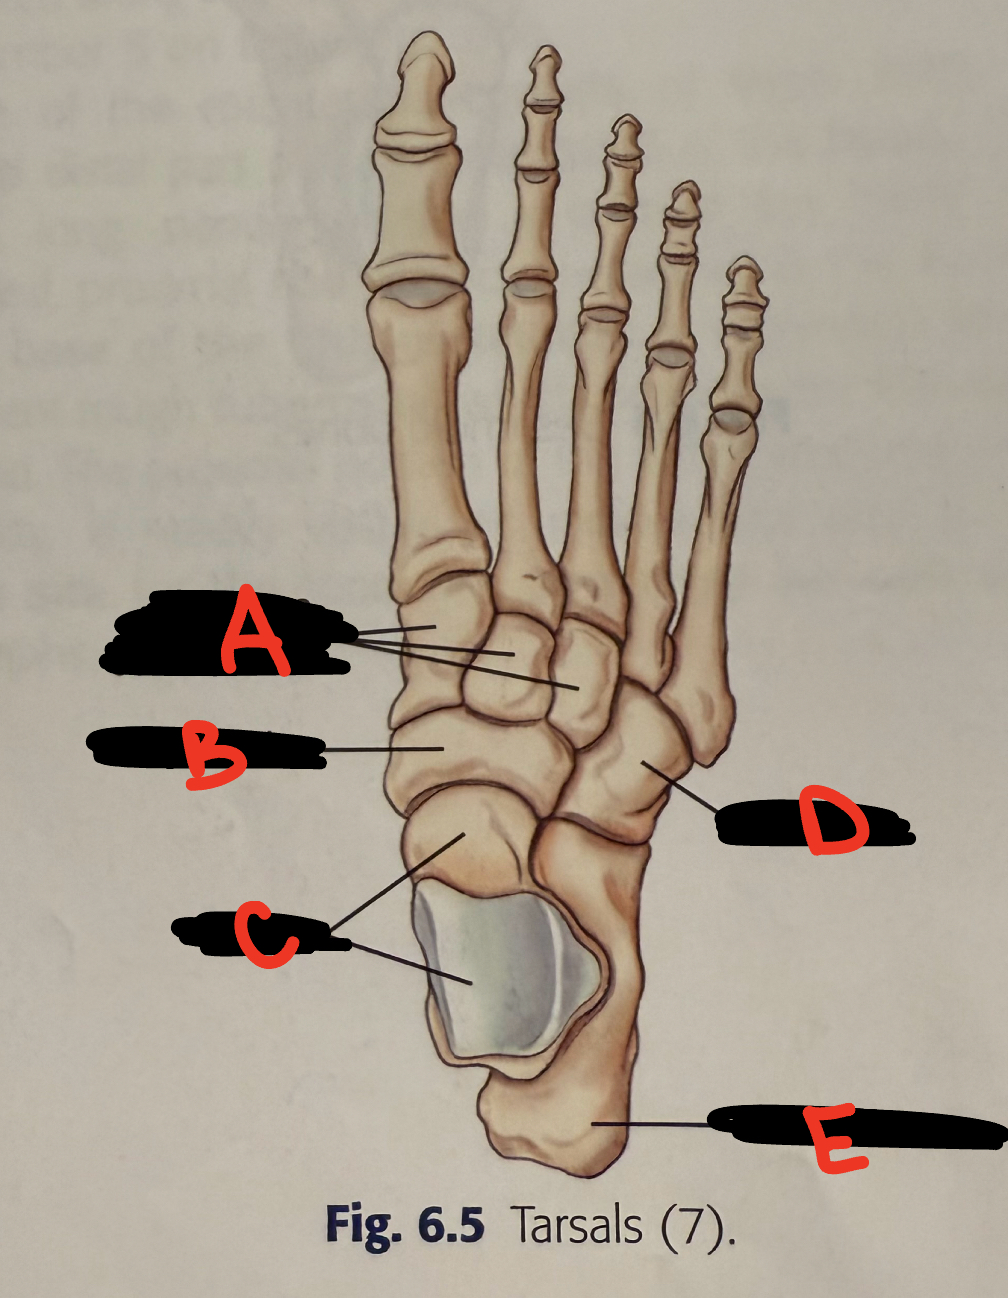

anterior tubercle

8

New cards

<p>C</p>

C

lateral malleolus